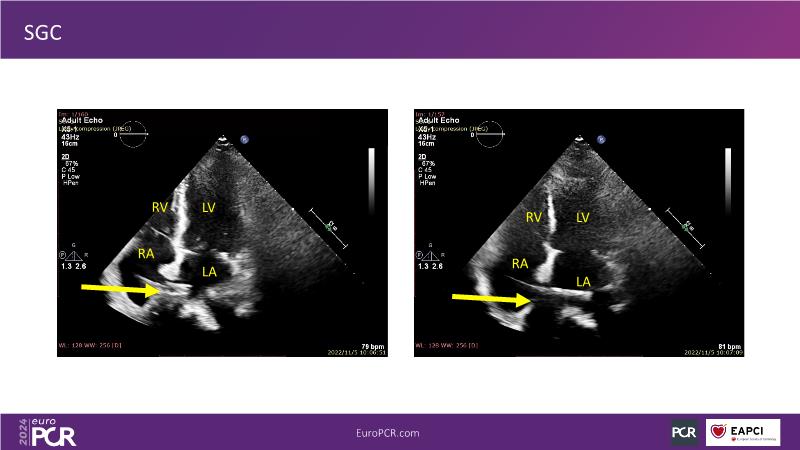

Watch this session to gain insights into the clinical evidence of mitral TEER therapy for the Asian population, learn techniques for implanting a MitraClip in patients with challenging anatomy, and understand how to use the four clip sizes for optimal outcomes. The session also covers educational aspects of clipping in dextrocardia, the benefits of reserve bending of the transseptal needle for tenting and puncture, new steering maneuvers for dextrocardia patients, and the importance of understanding anatomy and collaborating closely with the echo team for success.